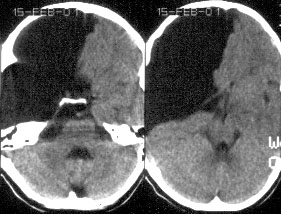

КТ-диагностика порэнцефалических кист головного мозга